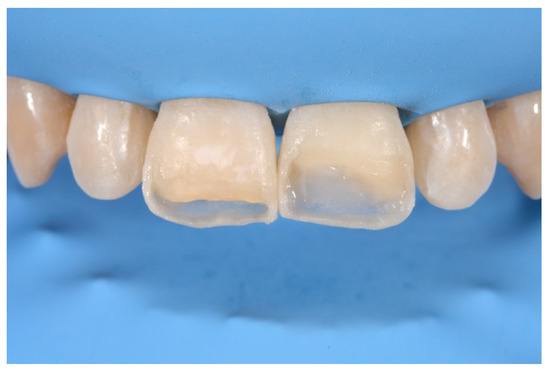

2. Case Presentation

- Molding palatal wall and incisal margin;

- Building interproximal walls with matrices;

- Layering free-hand buccal surface.